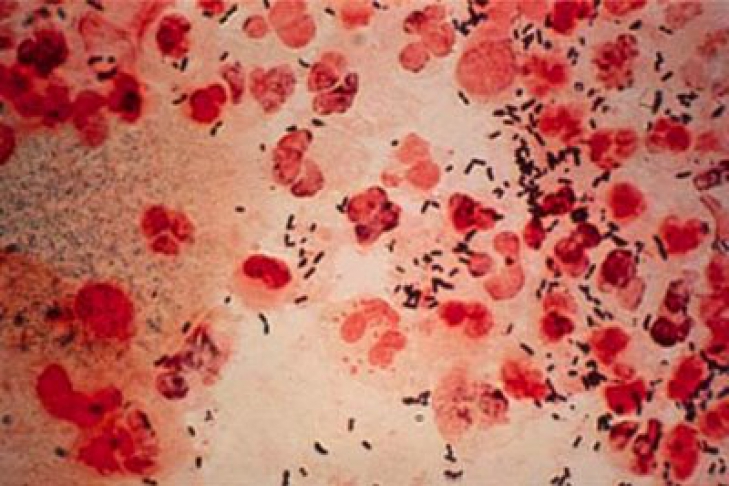

Возбудитель гонореи (Neisseria gonorrhoeae) - абсолютно патогенный организм. Neisseria gonorrhoeae прежде поражает эпителиальные ткани, поэтому, сначала инфекция развивается в мочеиспускательном канале, на шейке матки и прямой кишке. Но потом венерическая инфекция поражает различные органы, в том числе костную, дыхательную, сердечнососудистую и нервную системы. Нередко из-за гонореи развивается мужское и женское бесплодие.